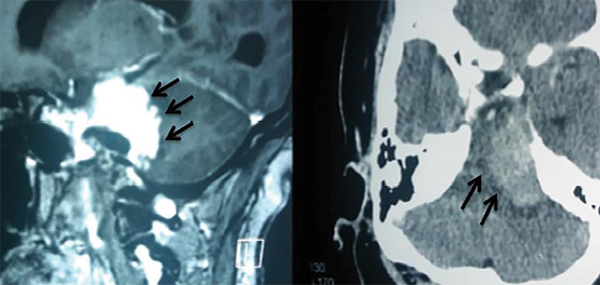

Por definición, los meningiomas petroclivales tienen su origen medial a los pares craneales V, VII, VIII, IX, X y XI, y pueden alcanzar el tentorio.1,3,5,6 A menudo se extienden hacia la fosa media, el seno cavernoso y la cisterna prepontina (Figura 1). Pueden descender al agujero magno, pudiendo invadir la piamadre y causar compresión del tronco encefálico. En los casos en que hay edema del tronco encefálico (hipodensidad en la tomografía o hiperseñal enT2 en la resonancia magnética) o una forma dentada e irregular del tumor sobre el tejido cerebral, la extracción total es muy difícil o imposible sin causar déficits neurológicos3-5(Figura 2). Los meningiomas del clivus inferior (foramen magno), petrosos, tentoriales y del ala esfenoidal pueden alcanzar estas áreas, pero no se consideran de origen petroclival.6

Figura 2: Resonancia magnética que muestra la forma dentada del borde del tumor (izquierda) y tomografía que muestra edema del tronco encefálico. Éstos son hallazgos que indican la ausencia de un buen plan de disección entre el tumor y el tronco encefálico.